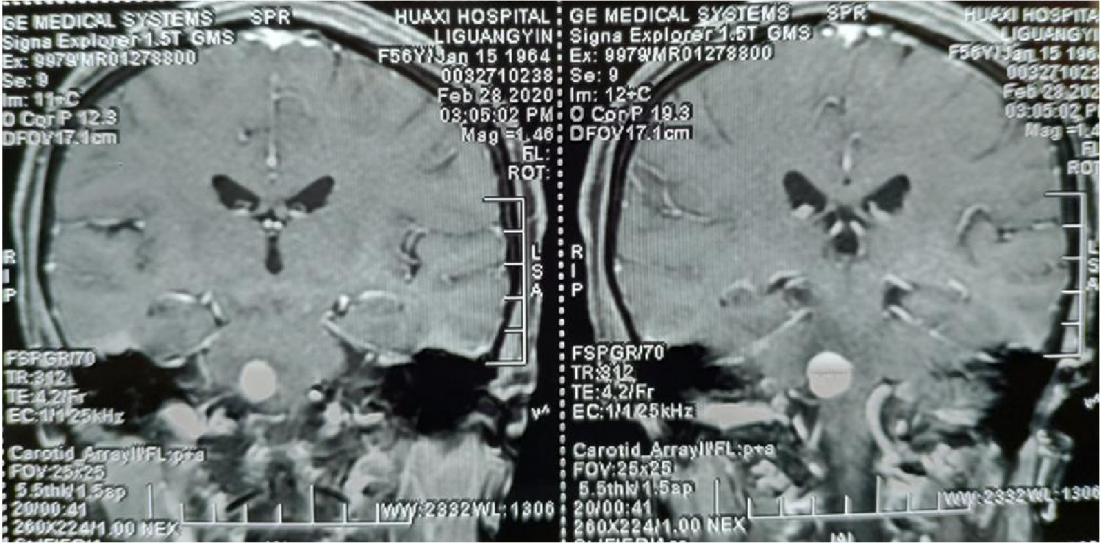

MR显示桥脑右侧高信号影,肿瘤位于四脑室界沟上方之桥脑部分,邻近面丘及动眼神经核,因此患者出现面瘫。

肿瘤位于桥脑与延髓交界处

面神经丘受压明显